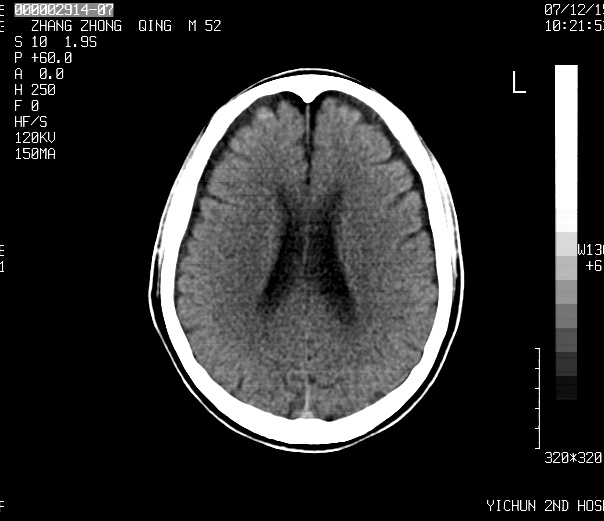

考虑    四叠体池脂肪瘤。脑萎缩

1)四叠体池脂肪瘤.2)脑萎缩.

2、脑萎缩。